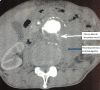

Scanner abdominal, coupe transversale